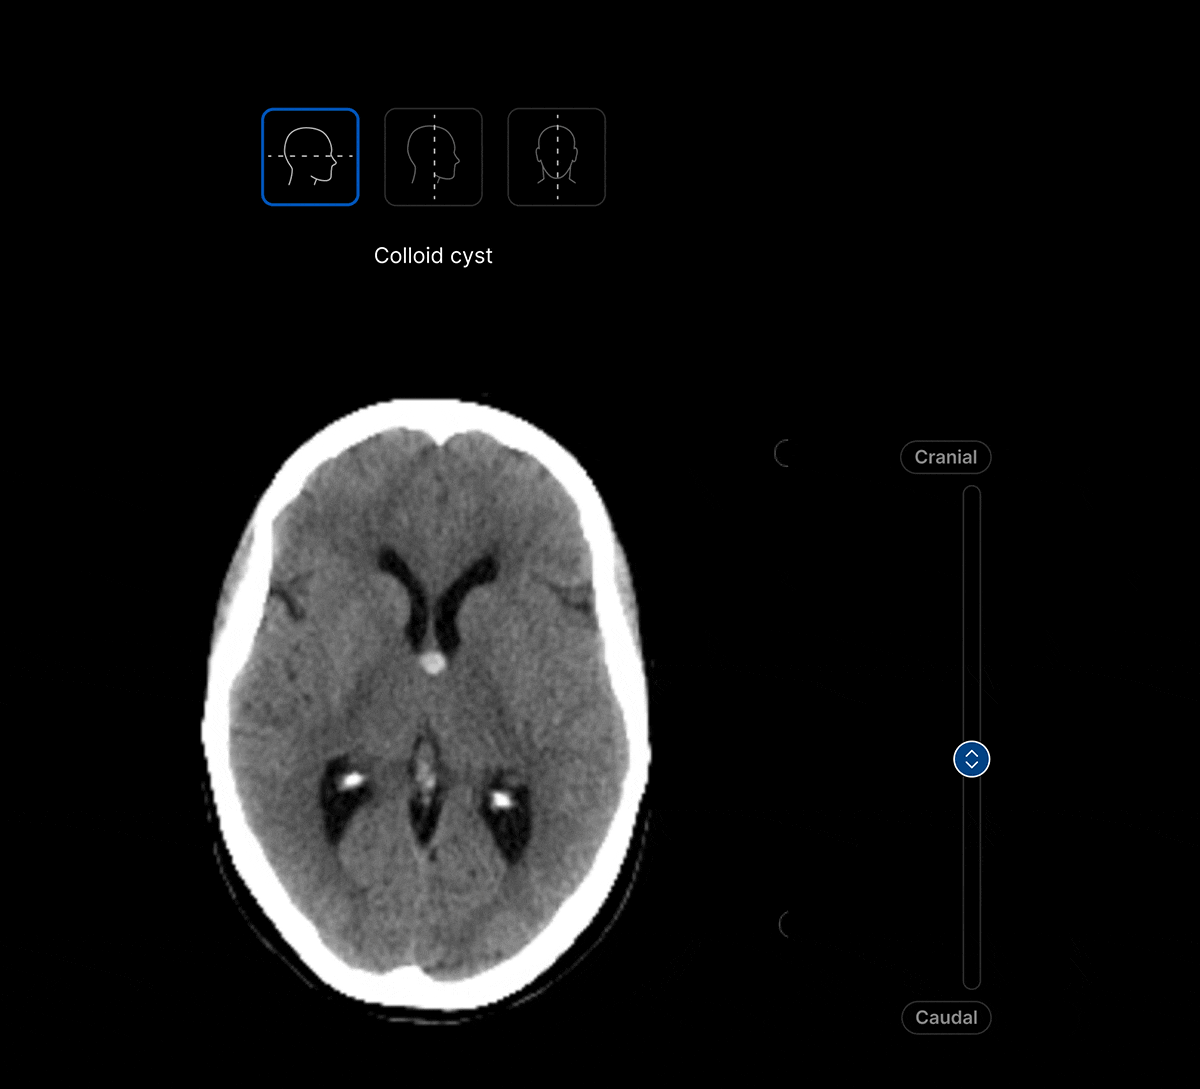

The UI integrates seamlessly with PACS/ RIS, displaying a resizable, no-click overlay window with findings and localisation.

Identifies up to 130 suspected head CT findings, grouped by urgency or other customisable criteria.

Coloured overlays on the image to quickly locate findings.

AI analysis viewable on different head CT slices.

View the findings in sagittal, axial and coronal projections.

View findings within preset subdural, bone, brain, soft tissue and stroke views to provide additional context to the AI results.